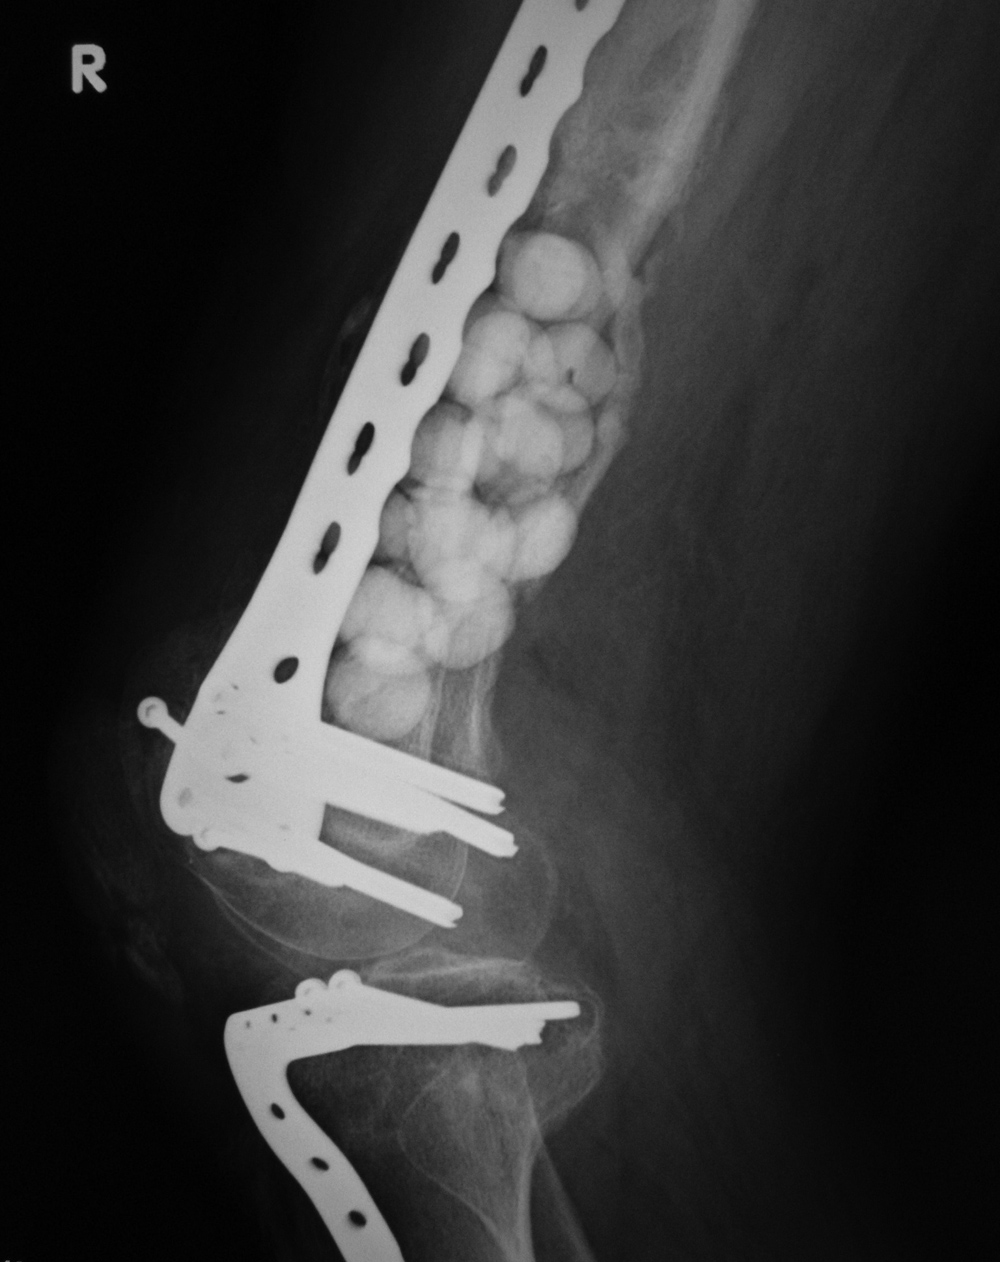

Metastatic renal cell carcinoma with pathologic fracture

Metastatic renal cell carcinoma pathologic fracture treated with curettage, bone cement, femur intramedullary nail, and distal locking screws

Bone cement in metastatic renal cell sarcoma